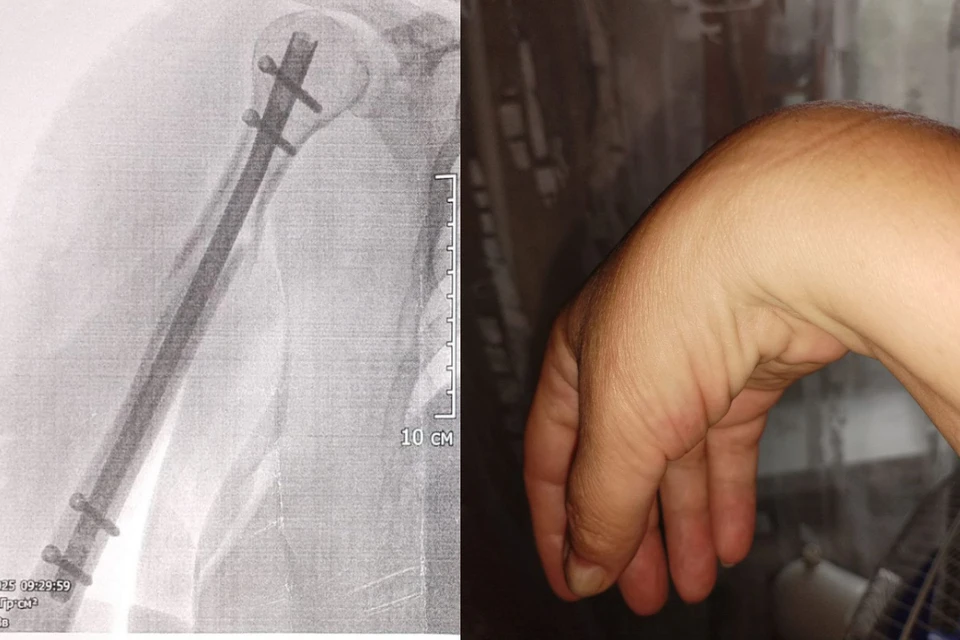

- 1 апреля мне сделали первую операцию, установили титановый стержень с болтами и закрепили кости плеча. Вторая операция была через две недели: устраняли посттравматический невроз. Сказали, что все прошло нормально. Но правая кисть у меня осталась парализована с момента травмы: я не могла работать, даже есть было трудно, - говорит Оксана.

- После перелома плечевой кости и операции по синтезу кости у Оксаны повисла кисть и перестали разгибаться пальцы. Это произошло из-за повреждения лучевого нерва: у пациентки были парализовало мышцы, которые отвечают за сгибание и разгибание пальцев. Коллеги из Новосибирска успешно провели ей остеосинтез, прежде чем она попала к нам, - сообщил Андрей Байтингер, врач-нейрохирург Томского НИИ Микрохирургии. – Но на нашей операции мы обнаружили выраженное рубцовое сращение нерва с металлом и окружающими тканями и решили провести невролиз лучевого нерва.